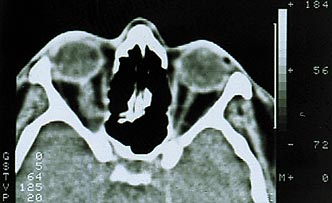

Рис. 3. Компьютерная томограмма больного с эксцентричным ростом менингиомы зрительного нерва.